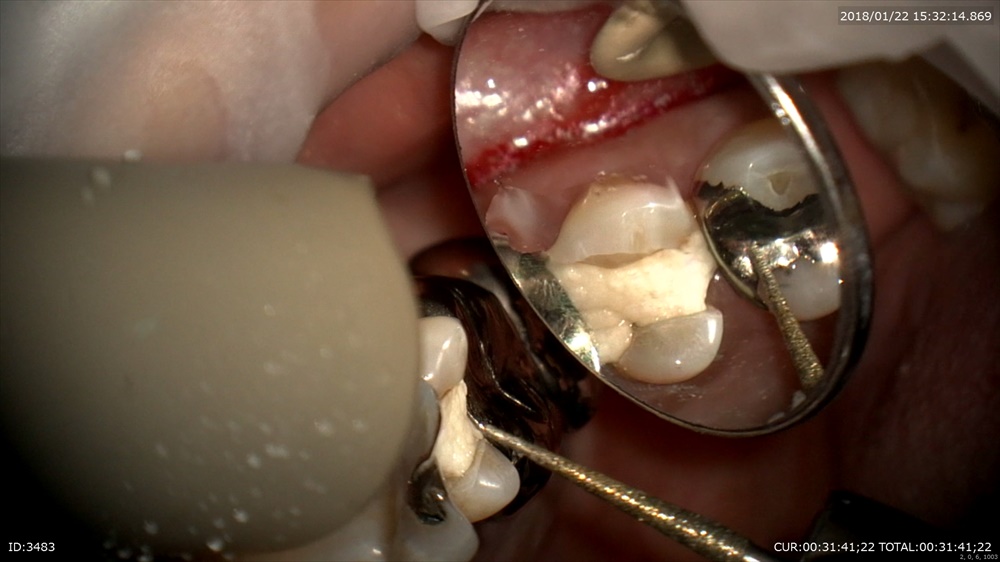

次はむし歯

銀歯むし歯の恐ろしさ。。。

銀歯が取れたで来院。歯科ドックで歯茎の中までむし歯と診断しました。

丁寧に。深い。歯茎の中まで。銀歯の恐ろしさ。。